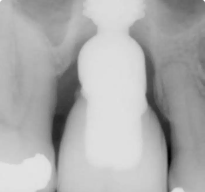

Caso Bicon: Seguimiento radiográfico de siete años de un implante Bicon SHORT® de 6,0 x 5,0 mm con un pilar de elevación de seno y una corona de pilar integrada (IAC)

Seguimiento radiográfico de siete años de un implante Bicon SHORT® de 6,0 x 5,0 mm con un pilar de elevación de seno y una corona de pilar integrada (IAC)

Presentamos el caso de un paciente masculino de 69 años, en el que se realizó la extracción dental seguida de la colocación de un implante Bicon SHORT® de 6,0 x 5,0 mm con pilar de elevación de seno.

El caso se restauró con una corona de pilar integrado (IAC) de 20 mm de longitud y ha sido seguido durante 84 meses.

Este caso destaca no solo por la estabilidad a largo plazo del implante corto, sino también por mostrar de forma radiográfica la aplicación de la Ley de Wolff: el hueso se adapta y se refuerza en respuesta a la carga funcional.